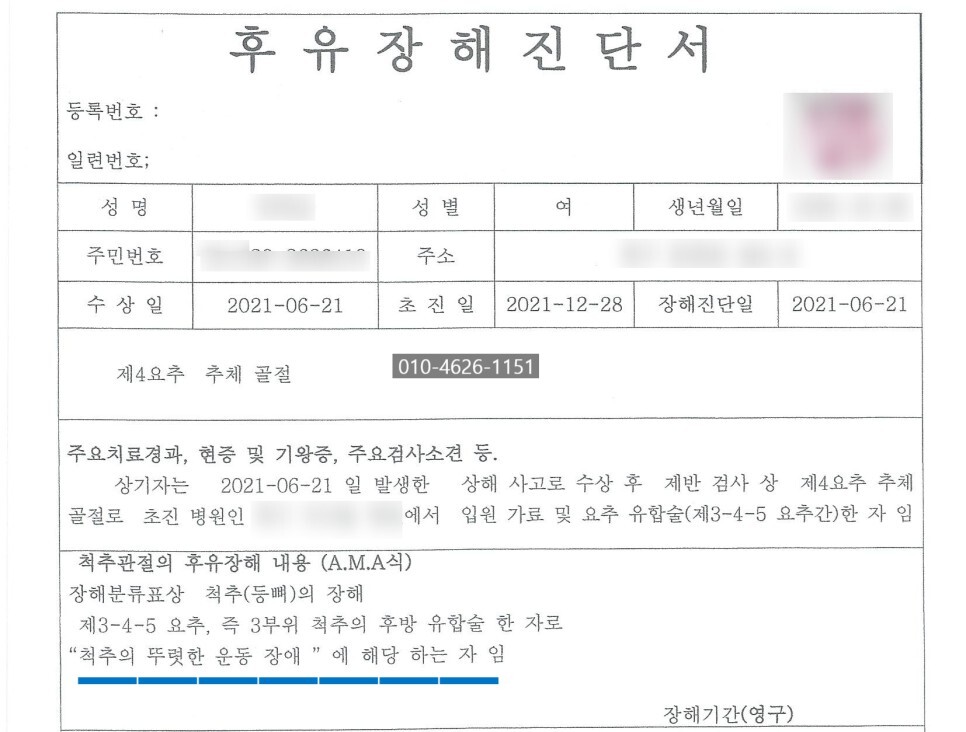

사고 이후 6개월 경과 후 후유장해

진단 위해 병원 내원하였고,

'척추의 뚜렷한 운동장해(장해율 30%)'

'척추의 중도의 운동장해(장해4급)'

후유장해진단서 발급 하였습니다.